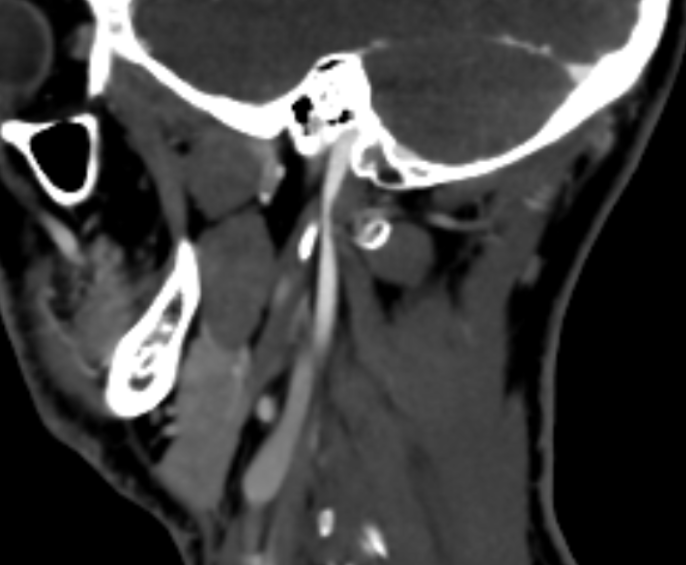

@Rob12345 I can help you get a better look at the IJV compression at the level of C1.

If you go into your original CT imaging, go to the axial view. Then scroll to C1. I’ve attached my own imaging to help you know what to look for.

@Rob12345 can you go into the axial view of the original imaging and go to C1? It’s the best view for showing IJV compression by C1 and styloids. I’ve attached my own imaging to help you find C1 in the axial view.

@Rob12345 - I can see you have bilateral IJV compression in the images you’ve posted & it’s possible the middle image in your first set of pictures is pointing to collateral veins. I’m not great at identifying collaterals, but I can say for sure your IJVs are being squashed between your styloids & C1.